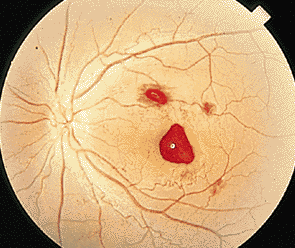

對于很多患者而言,玻璃體變性主要原因就是隨著年齡不斷增加,新陳代謝不斷變緩,使得玻璃體自身變性。比如像星狀玻璃體變性,常常見于50歲以上,不過它只是引起視力的不適,并不會導(dǎo)致視力下降。因為玻璃體內(nèi)新陳代謝緩慢,而出現(xiàn)了含鈣的脂質(zhì)白色小球。而玻璃體變性中更為嚴(yán)重的是出現(xiàn)液化現(xiàn)象,特別是閃輝性玻璃體液化,由于嚴(yán)重眼外傷和手術(shù)后眼內(nèi)出血導(dǎo)致的玻璃體或前房會出現(xiàn)無數(shù)黃白色和其他顏色的膽固醇結(jié)晶。

對于玻璃體混濁這樣復(fù)雜的癥狀,一般的眼科醫(yī)院無法根治,由于眼睛玻璃體的特殊性,目前尚無有玻璃體變性的特效藥,只能經(jīng)過長期的治療和鞏固,使得玻璃體不會出現(xiàn)其他病變。所以對于病情較為嚴(yán)重的玻璃體變性患者而言,就像因為變性引發(fā)的視網(wǎng)膜剝離或玻璃體出血等等,這些會出現(xiàn)視力嚴(yán)重減退,眼睛發(fā)紅、疼痛、畏光等等,一定要到專業(yè)的眼科醫(yī)院進(jìn)行醫(yī)治,比如在廈門眼科醫(yī)院的眼底專科,常年來除了眼底病之外,玻璃體變性治療領(lǐng)域在全國也是處于領(lǐng)先位置。